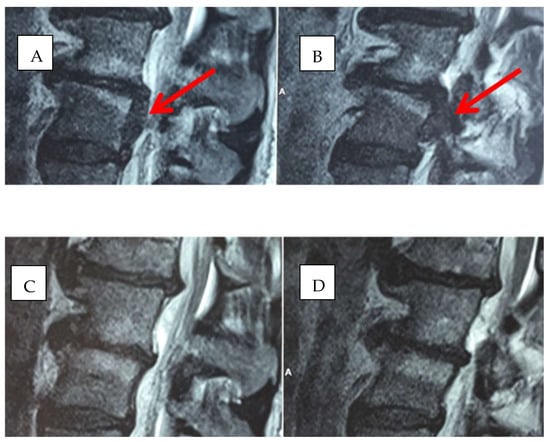

2.1. Infiltration Technique